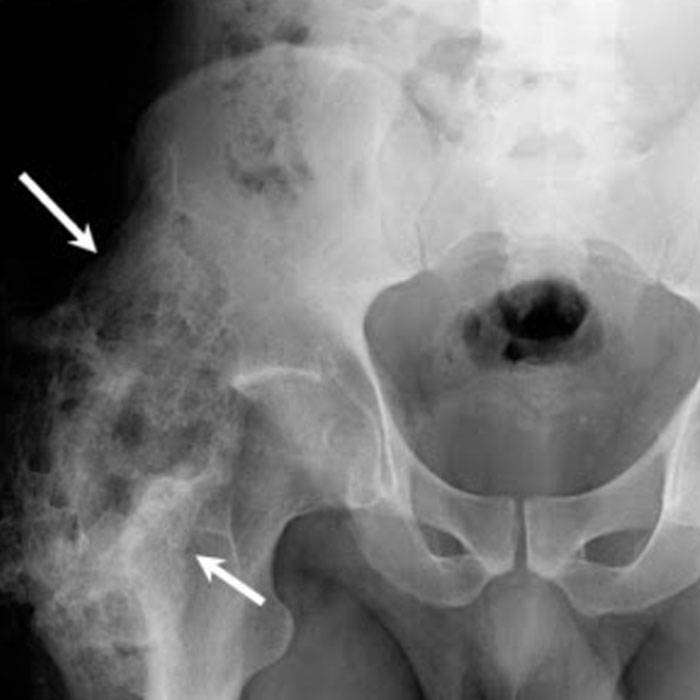

Kemik dokusunun meydana gelmesi durumudur. Kemikleşme olarak da tanımlanan ossifikasyon, normal veya hastalık sonucu oluşabilir. Kıkırdağın, minerallerin çökelmesiyle sertleşmesi sonucu kemikleşme ortaya çıkar. Normal kemikleşmede kemiğin kalınlığını artıran kemik zarı kemikleşmesi ve kemiğin uzunluğunu artıran kıkırdak içi kemikleşme vardır. Hastalık sonucu oluşan kemikleşmede ise yumuşak bir dokunun kemik dokusuna dönüşmesi durumu söz konusudur.